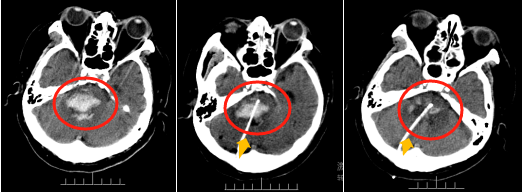

晚10点30分,完善术前准备后,有着数百例“立体定向颅内血肿穿刺”手术经验的吴善武首先对患者进行了“立体定向脑干出血软通道穿刺血肿清除术”,在精准定位的前提下对血肿部位进行穿刺,术中抽吸血肿约15ml,依据国际神经外科医生集团的分级标准,该患者的脑干出血程度达到最高级Ⅳ级以上,死亡率接近100%。f0816ef96b00022d49972525c81b383d.pngf0816ef96b00022d49972525c81b383d.png156386727049079221251294612.png

(上图分别为术前、术中及术后头部CT,其中红色区域为血肿区域,黄色箭头标记引流管。)

术后第二天,患者奇迹般地睁开了双眼,手术的成功意味着神经外科手术团队从死神手中抢回了一条性命。目前,患者生命体征基本稳定,已转回当地医院进行后续治疗。